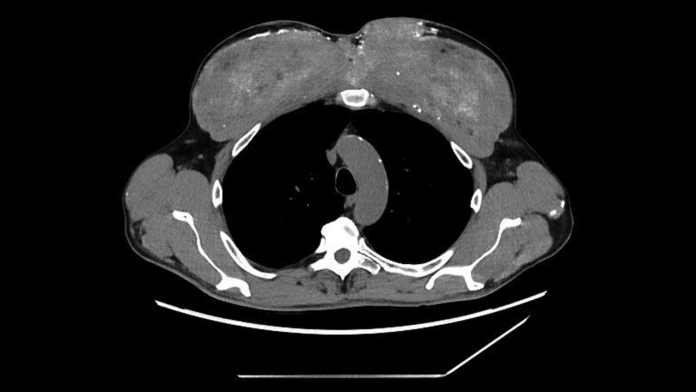

Ce s-a întâmplat apoi: Analizele de sânge au arătat că bărbatul avea niveluri crescute de creatină și uree, indicând că rinichii săi erau în faliment. Nivelurile de calciu din sânge erau, de asemenea, periculos de înalte. Scanările CT au relevat depozite de calciu în rinichi, pancreas și stomac, precum și zone cicatriceale în partea din spate și inferioară a plămânilor. Aceste scanări au arătat și schimbări neobișnuite în mușchii pieptului; aceștia păreau dens calcificați.

Diagnosticul: Sub microscop, mușchiul era umplut cu o substanță asemănătoare cu siliconul, pe bază de ulei, și înconjurat de depozite dense de calciu. Echipa a dedus că injecțiile musculare anterioare ale bărbatului conțineau probabil synthol, o substanță compusă în principal din ulei, care “umflă” vizual mușchii, umflându-i efectiv ca niște baloane cu apă.

În acest caz, syntholul a declanșat o reacție persistentă la corpul străin – corpul răspunzând esențial la materialul pe care nu-l putea descompune. În timp, această reacție a produs cicatrizare și calcificare, stocând cantități mari de calciu.